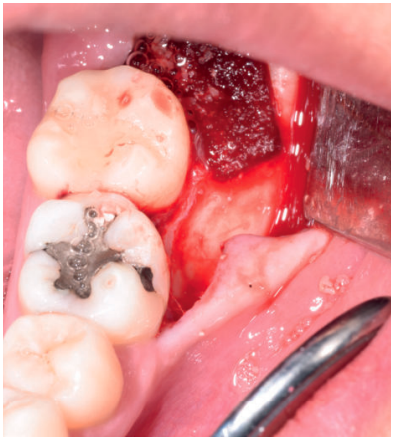

Tras obtener el consentimiento informado, se realizó un bloqueo anestésico mediante Articaína al 4% con adrenalina 1:100.000 del nervio dentario inferior y lingual, y posteriormente el nervio bucal. Se realizó una incisión festoneada lineal desde la cara distal del primer molar inferior izquierdo, hasta la cara distal del segundo molar inferior izquierdo, y se realizó una incisión oblicua hacia la rama ascendente mandibular. Tras el despegamiento mucoperióstico, se realizó una protección del nervio lingual durante las maniobras de ostectomía. Posteriormente se realizó la ostectomía necesaria para liberar el límite amelocementario del tercer molar inferior, procediendo a su luxación mediante botador recto, odontosección coronal con pieza de mano y fresa redonda de carburo de tungsteno, y exodoncia del fragmento radicular una vez retirado el fragmento coronal (Figura 2). El alveolo se lavó con suero fisiológico y se le hizo al paciente morder una gasa estéril empapada en clorhexidina al 0,12%, durante la preparación del material de injerto.

Los fragmentos coronal y radicular se limpiaron de restos de tejidos blandos, y secos, se introdujeron en la máquina Smart Dentin Grinder® (Kometa Bio, BIONER, España). Tras un ciclo de triturado de 3 segundos, y otro de tamizado de 20 segundos, el material obtenido (Figura 3) se limpió con la primera solución durante 12 minutos, y después durante 3 minutos con la segunda solución, para después transportar el material de injerto al alveolo, con presión controlada (Figura 4). Una vez compactado, se colocó una esponja de fibrina (Gelatamp® ) (Figura 5) y se suturó la herida con seda de 4/0, mediante dos puntos simples en la cara distal del segundo molar inferior izquierdo, un punto en cruz en la descarga y un punto en la papila (Figura 6). Se realizó una radiografía periapical intraoperatoria (Figura 7).